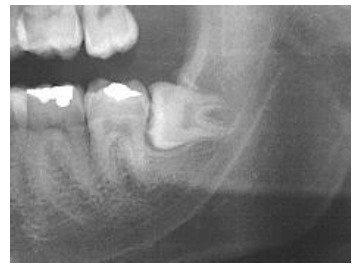

Quanto à classificação dos elementos impactados de Pell e Gregory, qual das afirmativas a seguir é a CORRETA para o elemento 38?